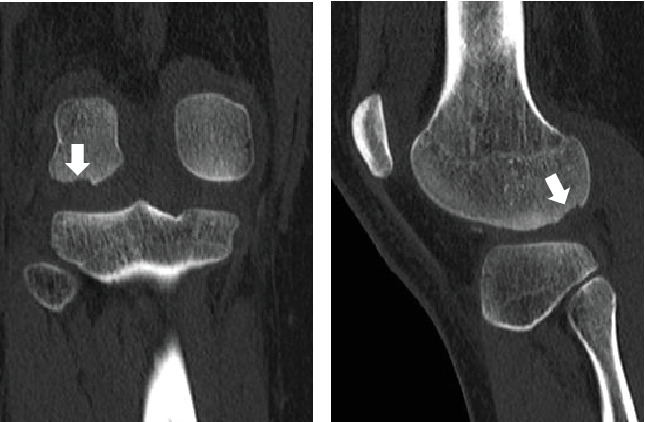

一个健康的16岁女孩在髌骨脱位后出现股骨外侧髁(LFC)后侧骨软骨骨折。骨软骨碎片固定及髌股内侧韧带重建均取得满意效果。据我们所知,这只是第三例报道的后LFC骨软骨骨折病例。然而,我们认为损伤机制与前两个病例不同。

A healthy 16-year-old girl presented with an osteochondral fracture of the posterior aspect of the lateral femoral condyle (LFC) following patellar dislocation. Satisfactory results were obtained with osteochondral fragment fixation and medial patellofemoral ligament (MPFL) reconstruction. To the best of our knowledge, this is only the third reported case of an osteochondral fracture of the posterior LFC. However, we believe that the mechanism of injury differed from that in the two previous cases.